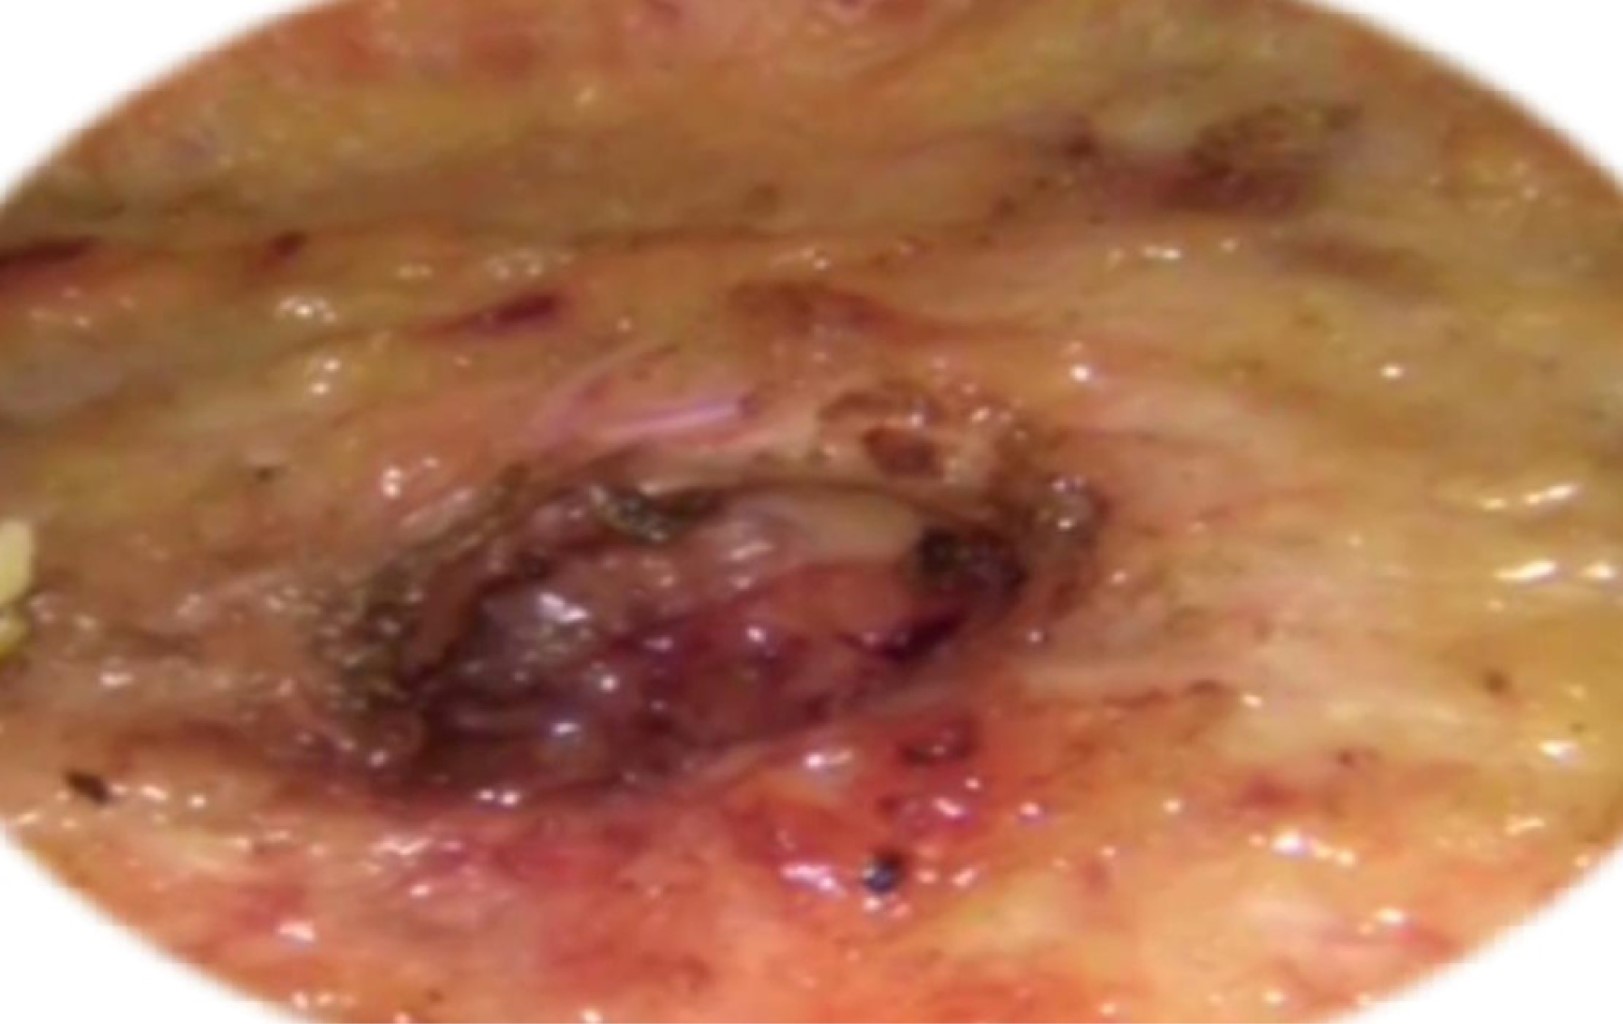

Se decide realizar un abordaje laparoscópico únicamente subcutáneo y colocación de material protésico de polipropileno, aceptando y firmando consentimiento informado. Se realizó tratamiento quirúrgico mínimamente invasivo asistido por laparoscopía, colocando trocares de trabajo de 10 mm suprapúbico y 2 de 5 mm en línea medioclavicular en cuadrante inferior derecho e izquierdo (Figura 1), encontrando defecto supraaponeurótico epigástrico de 2 cm y defecto umbilical de 3 cm (Figura 2). Se realizó cierre primario con puntos Smead Jones con sutura Monocryl® 2-0 (Figura 3) y se realizó plastia con técnica supraaponeurótica laparoscópica sólo subcutánea (SCOLA), con colocación de material protésico de polipropileno monofilamento (Figura 4). Se colocó Biovac® supraaponeurótico. Sin complicaciones transoperatorias, tiempo quirúrgico 60 min. Se egresó 48 horas después del evento quirúrgico, con adecuada evolución posquirúrgica, sin sangrado activo en los puertos laparoscópicos, no se palpan defectos aponeuróticos ni defectos herniarios a los seis meses del posoperatorio.

Figura 2